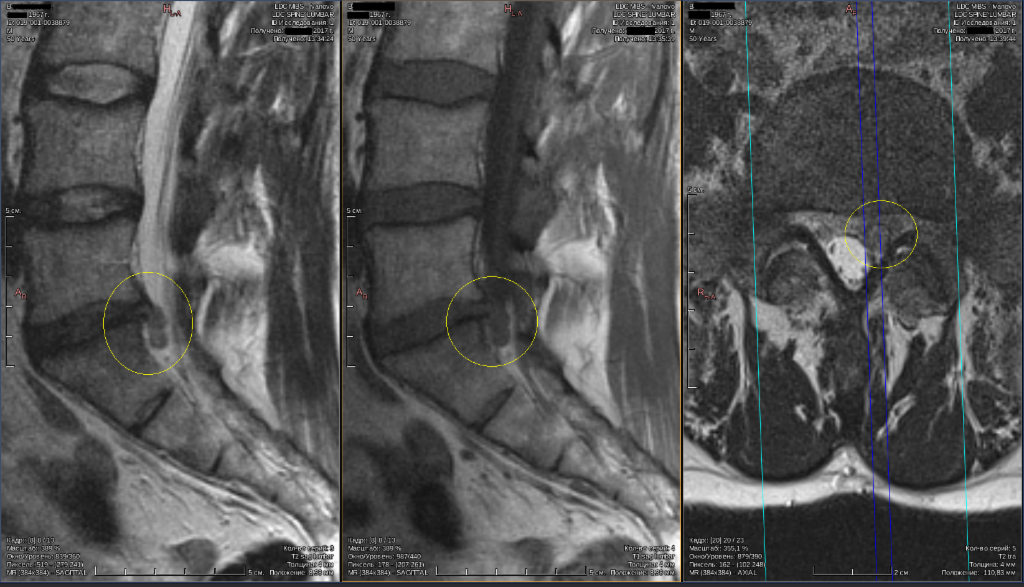

Протрузия l4 l5 лечение